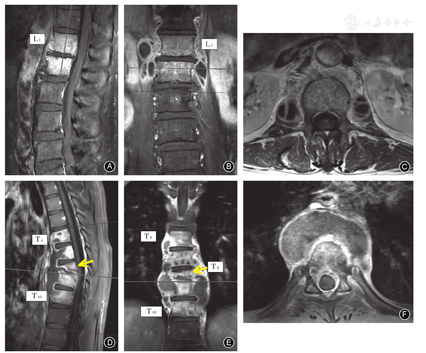

布鲁杆菌性脊柱炎在MRI的异常表现主要有[2,16,22,26]:当椎体的虫蚀样骨破坏明显时,T2WI呈不均匀较高信号;而在抑脂像,椎体、椎间盘、附件及椎管内呈不均匀高信号。可以发现椎管内脓肿、炎性肉芽组织突入椎管,抑或是破坏的椎间盘突入椎管。后纵韧带钙化导致相应平面脊髓受压。脓肿为椎旁条状或梭形异常信号影,位于椎前、两侧或椎体后方,脓肿壁呈薄而不规则的增强,且界限不清,无流注脓肿(图1A,图4A,表6)。本团队研究显示布鲁杆菌性脊柱炎较脊柱柱结核病灶内水分子弥散受限程度要高,ADC值的平均值较脊柱结核为低。

脊柱结核MRI显示界限清楚的椎旁异常信号,椎体骨质破坏,T1WI正常高信号的骨髓组织呈信号减低,被病变的低信号代替;T2WI由于病变椎体含水量增加,信号增强,椎体终板常受累,终板破坏致中断甚至消失,为脊柱结核的典型表现[17]。脊椎结核MRI最典型的特点是"跳跃病灶"和薄而光滑的强化脓肿壁(图1B,图4B),以及界限清楚的椎旁异常信号,椎体周围冷脓肿是诊断的重要依据(表6)[12,27]。